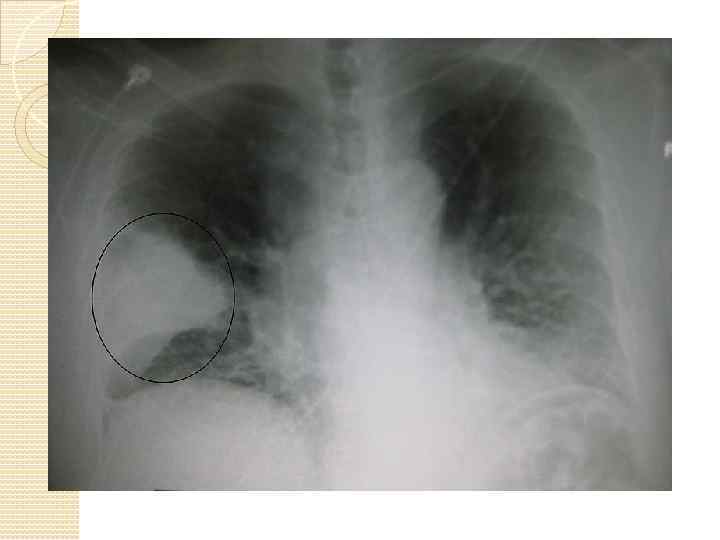

Клиникасы. Кейбір жағдайларда ошақты пневмония аяқ астынан пайда болуы мүмкін, көбінесе ол трахеобронхитпен немесе жіті респираторлық инфекциялармен қоса дамиды. Алғашқы белгілері дене қызуының көтерілуімен, жөтелдің күшеюімен, аз да болса іріңді-шырышты қақырықтың бөлінуімен байқалады. Егерде пневмония физикалық тексеру әдістерімен анықтауға болады. Бұл кезде дауыс дірілінің күшеюі, перкуторлы дыбыстың тұйықталуы, везикулярлық тыныстың қатаң түрі, ұсақ көпіршікті дауысты ылғалды сырылдар анықталады. Тереңдеу орналасқан ошақтың белгісі ретінде тек қана ылғалды, күшті дыбысты, ұсақ көпіршікті сырылдар естіледі. Сырылдардың жақсы естілуі бронх төңірегіндегі өкпе тінінің тығыздалуына тікелей байланысты болады. Қанда лейкоциттер формуласының сәл ғана сол жаққа ығысуы байқалады, лейкоцитоз аздап көбейеді. Рентген сәулесімен тексергенде өкпенің сегментарлы немесе полисегментарлы гомогенді қараюы анықталады, әдетте, олар өкпенің төменгі бөліктерінде орналасады.

Диагностикалық критерийлері: Ұзақ фебрильді қызба. Интоксикация белгілері. Тыныс алу жетіспеушілігінің белгілері- ентікпе, цианоз, тыныс алуға қосымша бұлшықеттердің қатысуы. Тұрақты жергілікті өзгерістер: Аускультативті-ұсақ көпіршікті ылғалды сырылдар, перкуторлы-қабынған жердің үстінде дыбыстың қысқаруы. Рентгенографияда-көлеңкелер. ЖҚА-де- нейтрофильді лейкоцитоз, ЭЖТ-ның жоғарылауы.

Интерстициалды пневмониялар. 1946 жылы Р. Ленк жедел ағымды пневмониялар арасынан төмендегі рентгендік сипаттарымен ерекшелінетін пневмонияларды бөліп шығарды: Өкпе суретінің өзгерісі кеңейген түбірден ұршық тәріздес тарайтын, тұрпайы не нәзік жолақтардан тұрады. Бұлардан негізінде бронх-төңіректік инфильтрация және, мүмкін, бронхтардың экссудатпен толуы жатады. Пневмония бар өкпе суреті ұялы әр түрлі көлемді тор тәрізді болады. Осы екі түрлі өзгерістердің үстіне кішілеу ателектаз ошақтары пайда, ұсақ дақтар көрінеді. Жайылмалы, тартылған жіп тәріздес айқын көрінетін көлеңкелер бронхтар қысылуының белгілерімен бейнеленеді. Осы пневмонияларды олинтерстициалдық деп атады. Балаларда сирек, жедел ағымды пневмониямен ауыратын балалардың 1%-да ғана кездеседі.